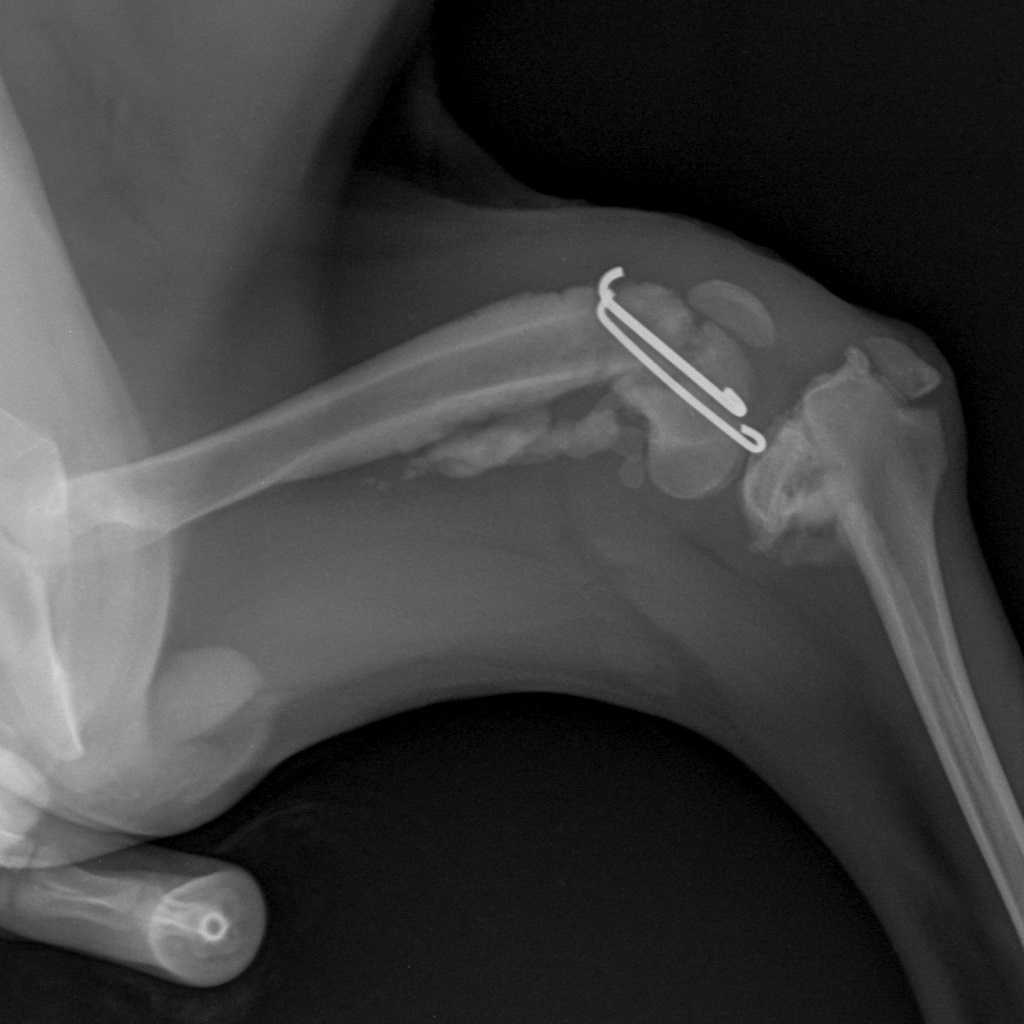

Вот такая бяка у девочки((

Такой мерзкий перелом бывает при прямом ударе по колену

Жуть какой перелом! Далекому от медицины человеку - и то смотреть страшно. Впрочем, неудивительно если её из машины на ходу выкинули.

А подсобрать получше эти обломки невозможно, слишком тоненькие косточки?